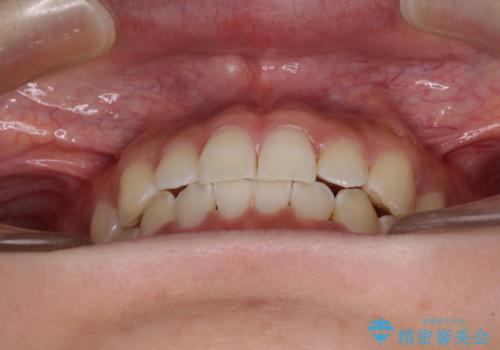

- 前歯の叢生と、奥歯の咬み合わせの悪さを気にして来院された患者様です。

左下には後続永久歯の欠損した乳歯が残存しており、叢生を相まって咬合関係が乱れていました。

乳歯は抜歯し、インビザラインにて矯正治療を行いながら、並行してインプラントによる補綴治療を行うこととしました。

矯正治療が終わるタイミングに合わせてインプラントの埋入を行っていたので、矯正治療を終了すると同時にセラミック補綴治療を行えました。

短期間でしっかりと治療を終えることができました。